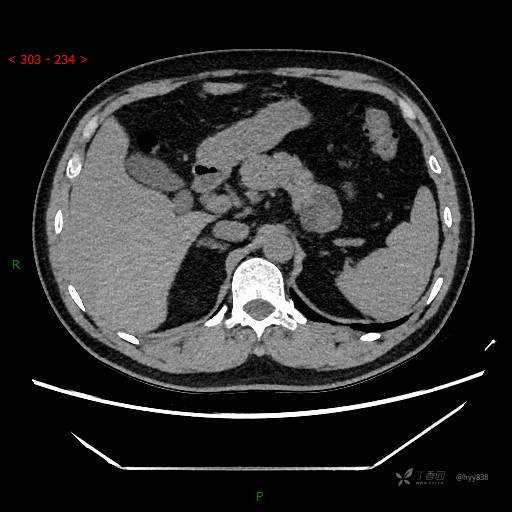

静脉期